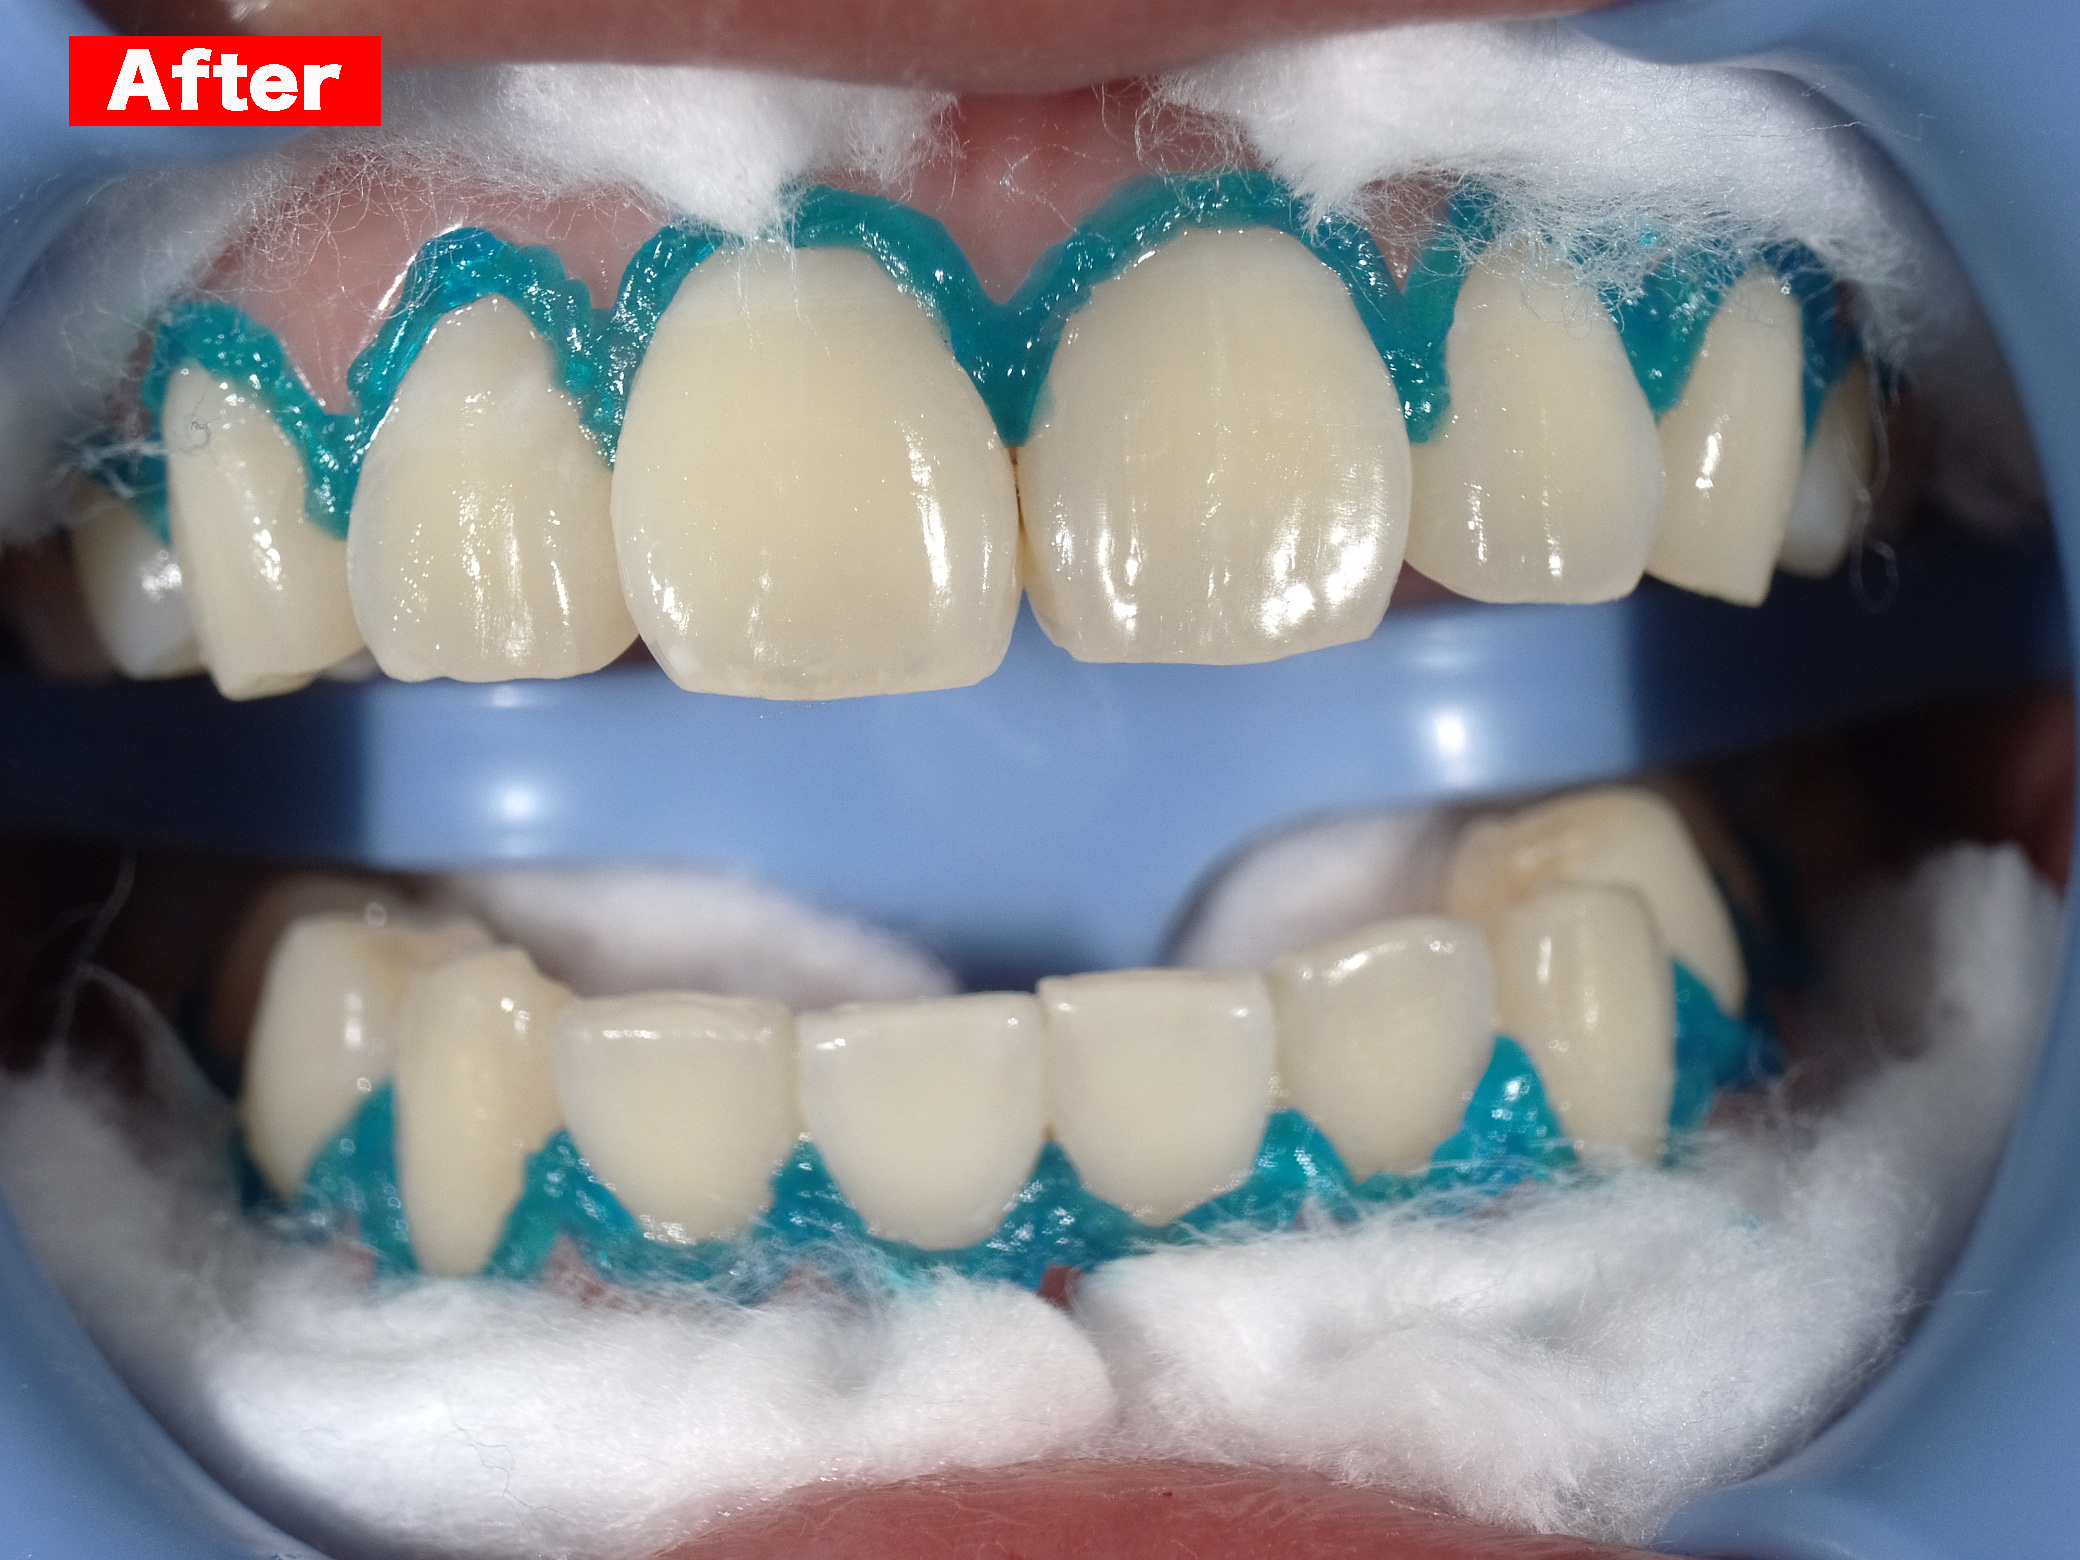

ホワイトニング

Case005 – ホワイトニングト

歯が欠けていて、隙間がある。

歯並びが気になる。

亀裂が入っている。

歯の無いところがある。

見える銀歯が気になる。

綺麗な口元になりたい。

という患者様の診療です。

上はジルコニアセラミックでかけているところを修復しながら、綺麗な歯並びで、患者様のお好きな白い歯に。

下の歯の無い所にはインプラント。

見える銀歯は外して綺麗な歯に修復。

また、ホワイトニングをして上の歯との色のギャップを少なくして、明るい口元にしました。